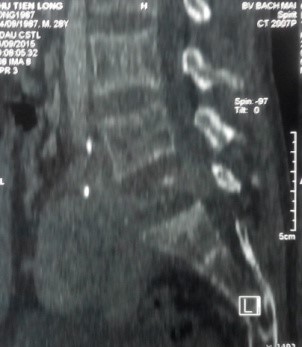

Trên X-quang, CT scanner khối u phá hủy vỏ xương gần hết thân và cuống sống L5.

Trên MRI, khối u giảm tín hiệu xâm lấn nhiều ra phía trước vào tiểu khung, xâm lấn ra phía sau chèn ép vào ống sống. Khối u ngấm thuốc mạnh, tăng sinh mạch nhiều trên phim MRI có tiêm thuốc.

CT scanner và MRI giúp đánh giá vỏ xương, tổn thương hủy xương cũng như mức độ thâm nhiễm quanh u. Trên T1W, T2W khối u TBKL đồng tín hiệu với tổ chức cơ, có thể giảm tín hiệu do collagen và hemosiderin, T1W sau tiêm ngấm thuốc. Phần mềm quanh u có thể hoại tử nhiễm trùng, đặc điểm này thường không gặp trong nang xương phình mạch, có thể để chẩn đoán phân biệt [5,11,12]. Bệnh nhân của chúng tôi, khối u phá vỡ thân đốt L5, thâm nhiễm phầm mềm rộng chèn ép ống sống phía sau, khối u cũng thâm nhiễm rộng ra phần mềm phía trước vào tiểu khung kích thước lớn khoảng 10 x 10cm, khối u đẩy lồi và một phần ôm lấy ngã ba chủ chậu ra phía trước gây khó khăn cho việc phẫu thuật lấy bỏ khối u và là yếu tố tiên lượng tái phát cao sau mổ.